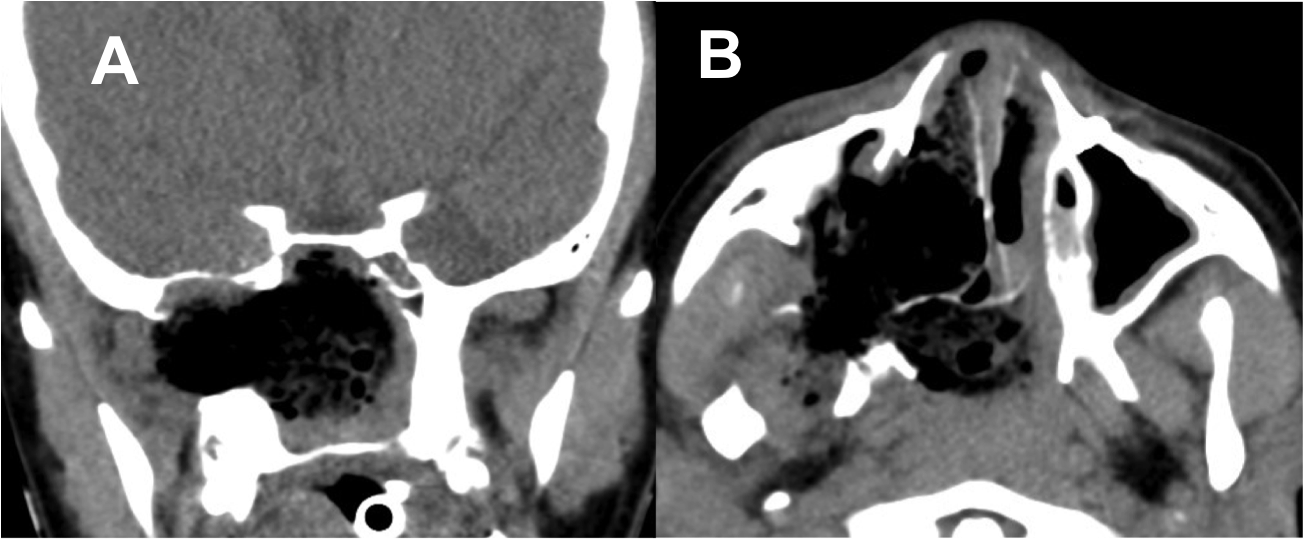

Introducción: La cirugía endoscópica endonasal se ha convertido en una herramienta fundamental para el manejo de patologías que comprometen la base de cráneo. En casos bien seleccionados, estas técnicas permiten resecciones quirúrgicas con una menor morbilidad sin comprometer los principios oncológicos de resección. Con el desarrollo de instrumental especializado, nuevas tecnologías y la experiencia de los cirujanos, la cirugía endoscópica endonasal se usa cada vez más en cirugía de base de cráneo en niños.

Diseño: Estudio observacional descriptivo de tipo serie de casos. Metodología: se describe la experiencia con pacientes pediátricos llevados a cirugía endoscópica endonasal para manejo de tumores de base de cráneo en el Instituto Nacional de Cancerología entre julio de 2014 y diciembre de 2016.

Resultados: Fueron intervenidos 8 pacientes entre los 2 y 14 años, con una edad promedio de nueve años y un seguimiento promedio de 16 meses. En el 75% se hizo una resección total del tumor. Un paciente requirió una reintervención y un paciente fue sometido a radiocirugía post-operatoria. 1 paciente falleció a pesar de múltiples intervenciones, quimioterapia y radioterapia.

Conclusión: La cirugía endoscópica endonasal para tumores de base de cráneo puede ser utilizada de forma segura en los pacientes pediátricos, es una técnica que en casos bien seleccionados pueden ofrecer excelentes resultados disminuyendo la morbilidad y complicaciones de las técnicas abiertas.

Chivukula S, Koutourousiou M, Snyderman CH, Fernandez- Miranda JC, Gardner PA, Tyler-Kabara EC. Endoscopic endonasal skull base surgery in the pediatric population. J Neurosurg Pediatr. 2013;11(3):227–41.

Banu MA, Rathman A, Patel KS, Souweidane MM, Anand VK, Greenfield JP, et al. Corridor-based endonasal endoscopic surgery for pediatric skull base pathology with detailed radioanatomic measurements. Neurosurgery. 2014;10(2):273–93.